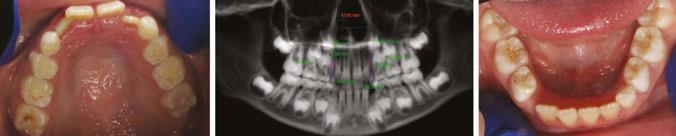

Figure 2A (top): Initial set-up in iOrtho. Figure 2B (bottom): Superimposition view of the initial set-up in iOrtho

Figure 3: Upper occlusal of the initial set-up versus upper occlusion clinical photo at 4 months

Figure 4: JA refinement records 4 months into treatment (10.11 years old). Upper and lower expanded. Refinement goals were to complete alignment and space consolidation and exaggerate U2 mesial root tip